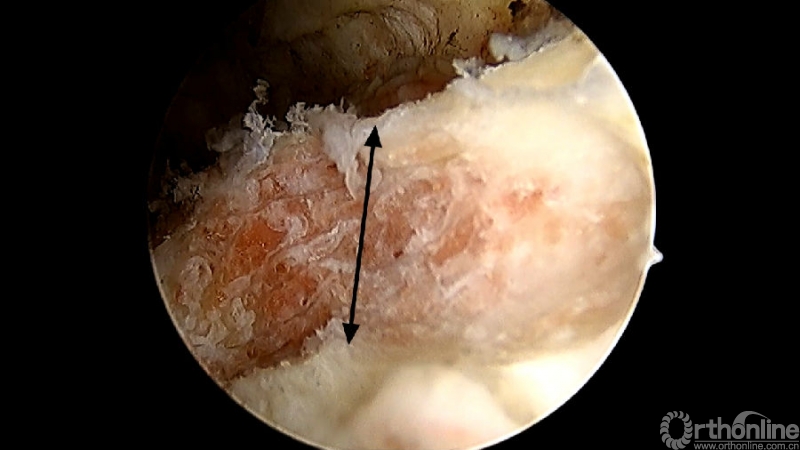

使用磨钻按照范围将下关节突内缘磨薄,然后用骨凿切除下关节突内缘显露出上关节突内缘及关节面。

术中切除下关节突内缘的范围